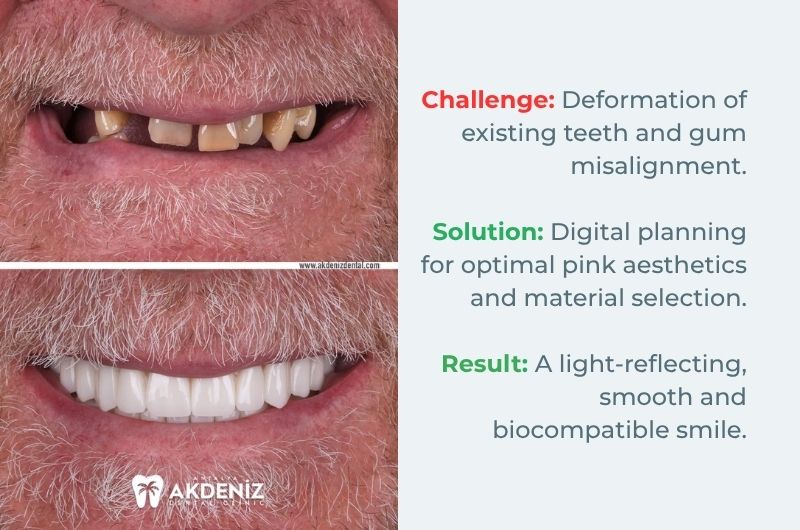

Aesthetic Architecture and Natural Harmony

Case Analysis 2:

In our second case, we aimed to clean the existing deformed teeth and fully stabilise the dental arch.

Key Detail: To break away from the perception of 'artificial teeth', the natural curves of the gums (pink aesthetics) were combined with the translucency of the porcelain.

Result: A smile design was achieved that is both natural and prestigious, perfectly suited to the patient's facial features.